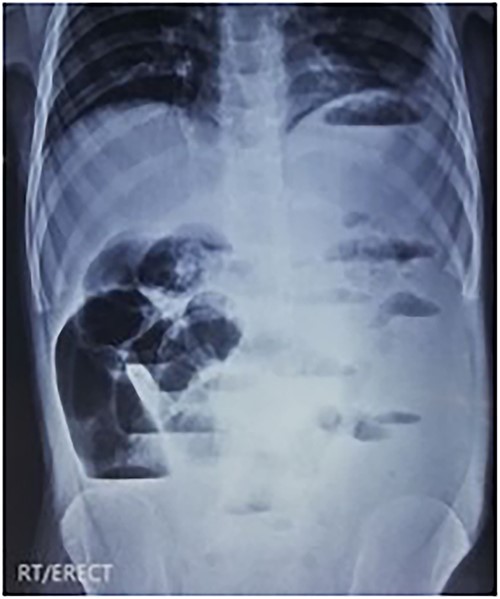

An erect X-ray abdomen (Fig. 1) showed multiple air-fluid levels and a distended bowel.

Radiological findings of ISK include a double closed-loop type obstruction, with multiple air-fluid levels in X-ray scans of the abdomen [3, 10]. These findings are often missed because ISK is a rare diagnosis, particularly in children [6]. Lee et al. [12] described two prominent and characteristic CT findings of ISK: (i) medial deviation of the distal descending colon and cecum with a beak appearance of the afferent limb of volvulus on its medial side and (ii) a “Whirl sign” formed because of the twisting of the intestine and mesentery.